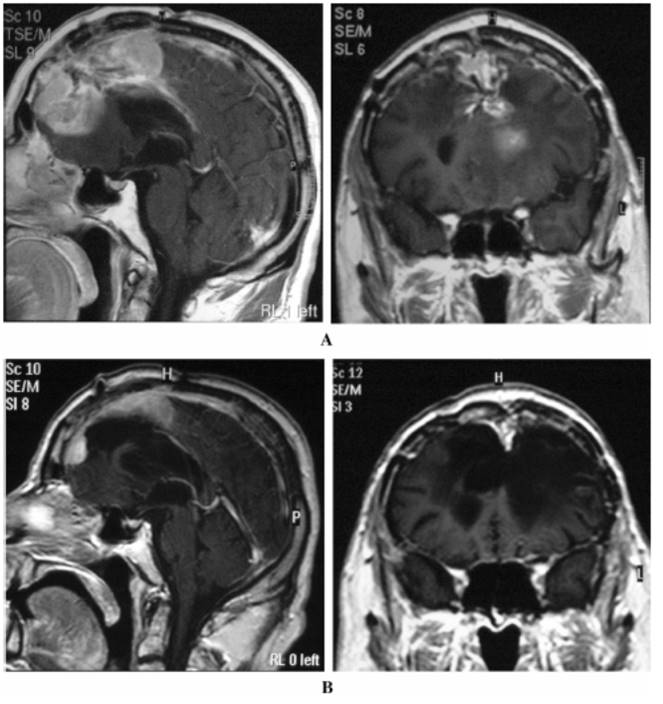

这是一个59岁的男性,2002年3月因为癫痫大发作,头部磁共振检查发现左侧额叶矢状窦脑膜瘤,做了“开颅肿瘤次全切除术”。2003年8月,发现肿瘤复发,做了第二次开颅手术。2004年8月,发现肿瘤第二次复发,第三次开颅手术后,他又进行了“适形放疗”+Hydroxyurea化疗,结果六个月之后肿瘤再次复发(下图A)。不光如此,由于肿瘤不断长大,他开始频繁癫痫发作,生活自理能力下降。

这一次大夫为他选择的是Temozolomide化疗,命运从此出现转机。治疗15个月,肿瘤体积缩小了60%(下图B),癫痫发作也减少了。